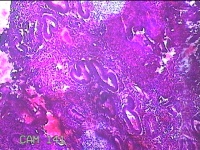

子宫腔赘生物(大)

性别

女

年龄

38岁

临床诊断

子宫内膜息肉;子宫异常出血

一般病史

月经量多数年,发现宫腔占位1个月。

标本名称

大体所见

灰白暗红色不规则肿物2.7x1.8x0.8cm一堆,切开肿物呈实性,切面灰白暗红色,质软。

图1

有那么点像子宫内膜息肉,片子这个效果,辩认起来非常困难。